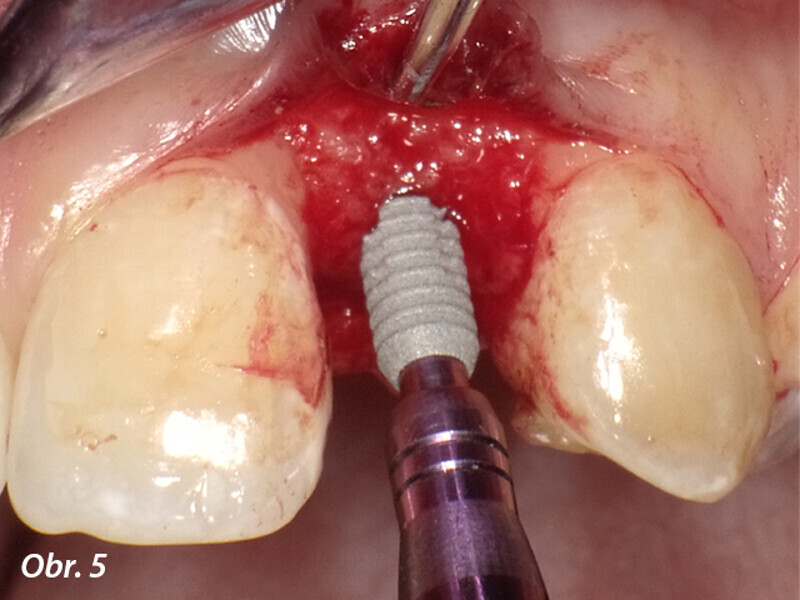

Aproximální rozšíření mezi kořeny zubů za účelem zavedení úzkého implantátu